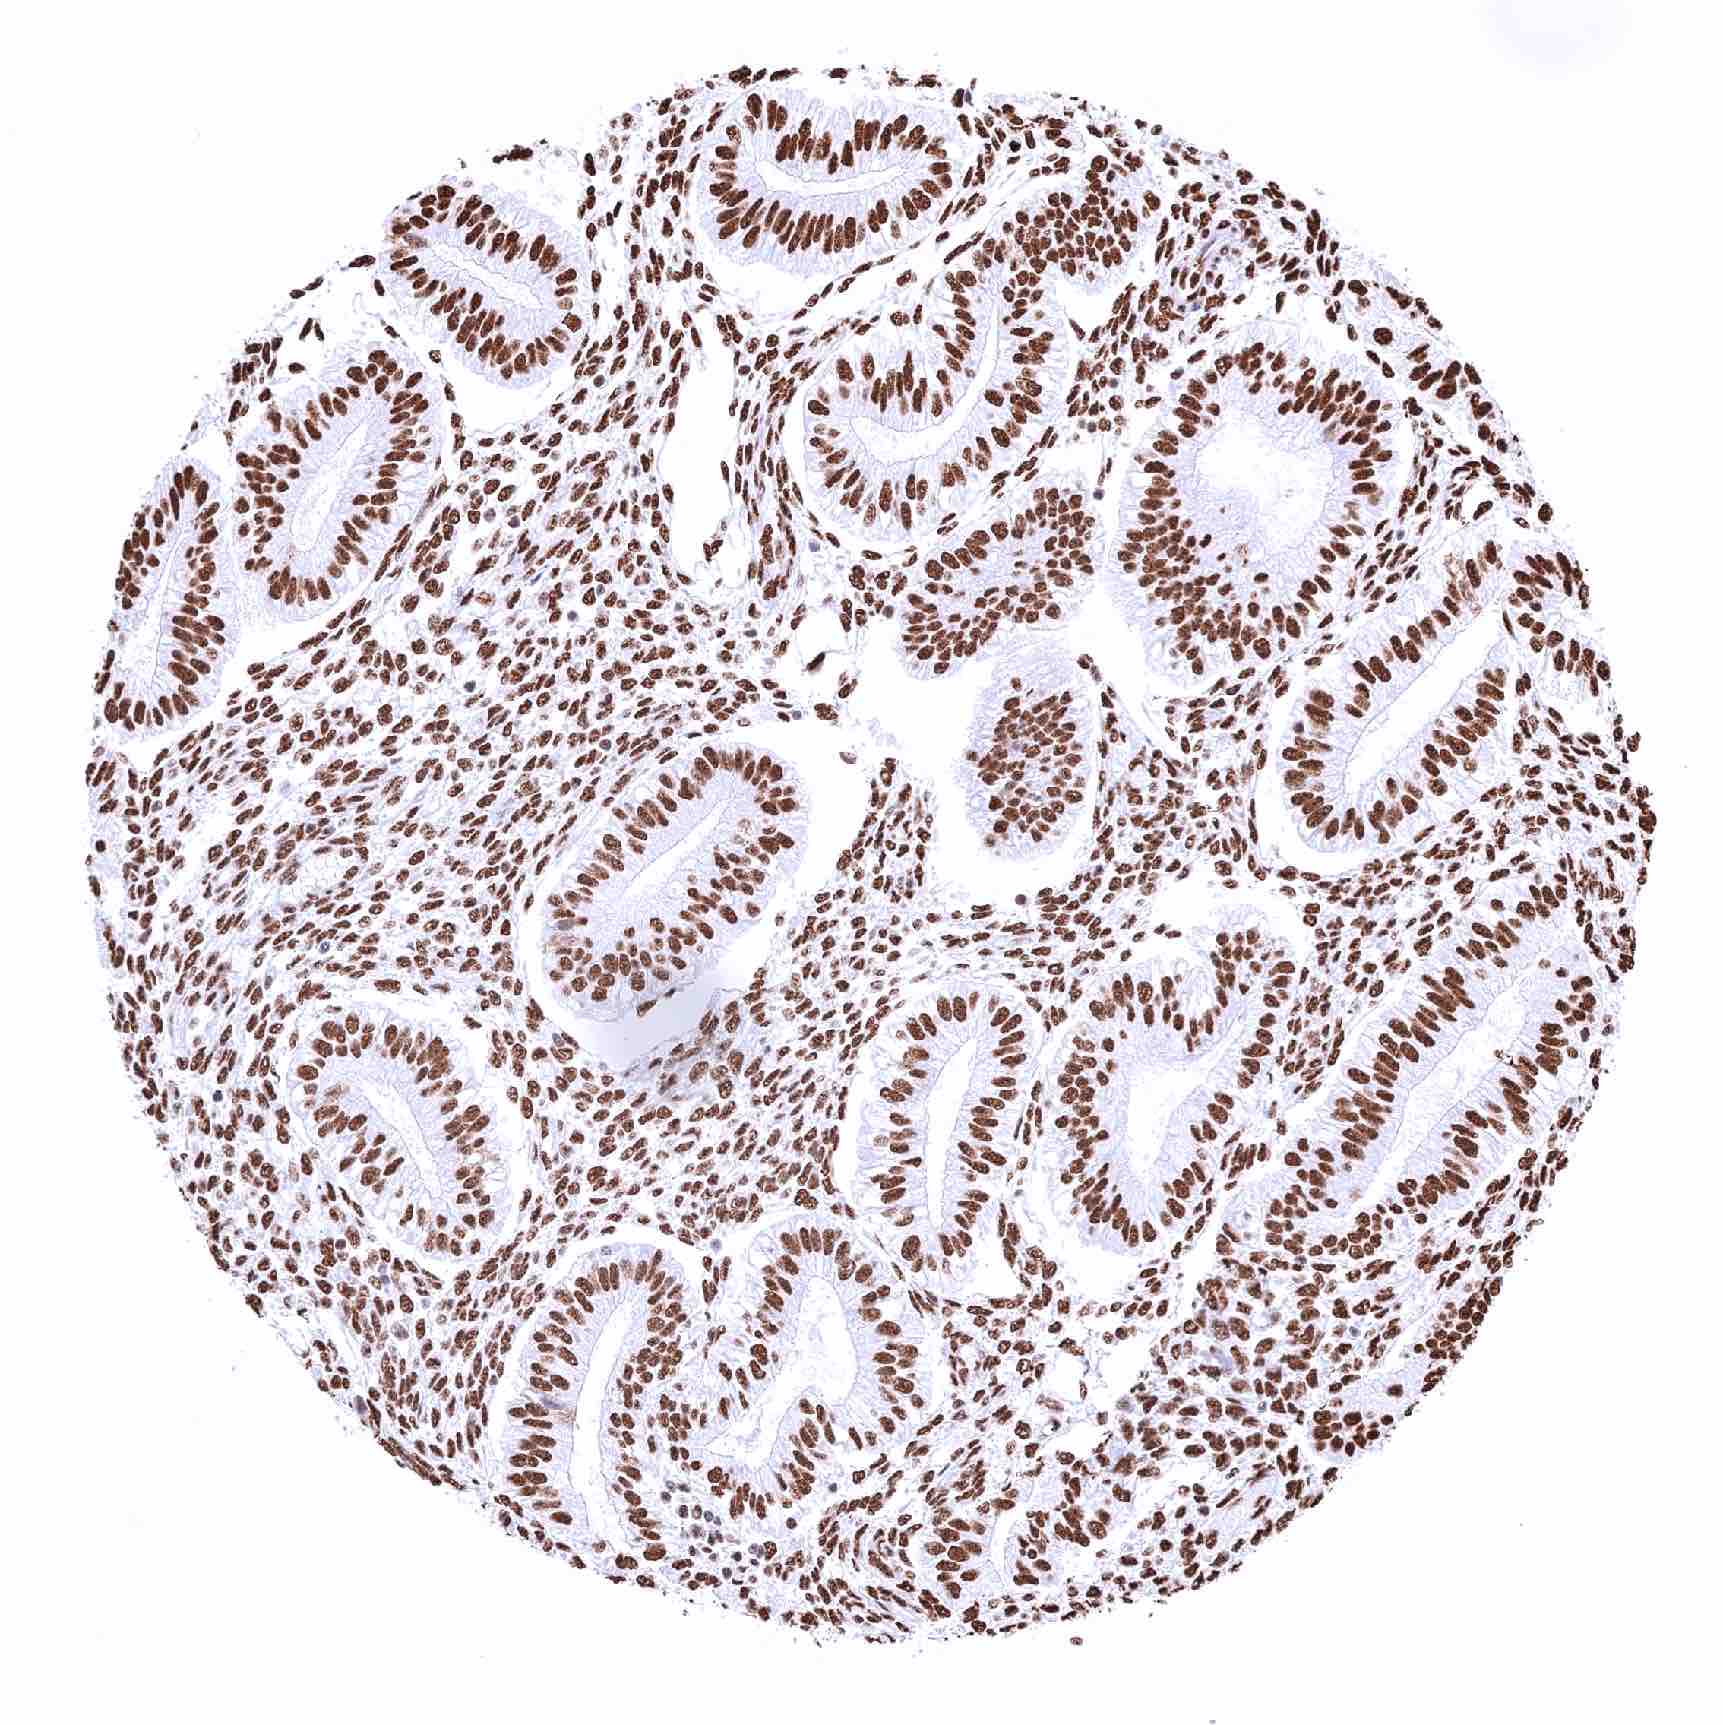

Colon descendens, mucosa – The intensity of nuclear TRIM28 staining decreases slightly from the crypt base to the surface epithelium

Colon descendens, mucosa